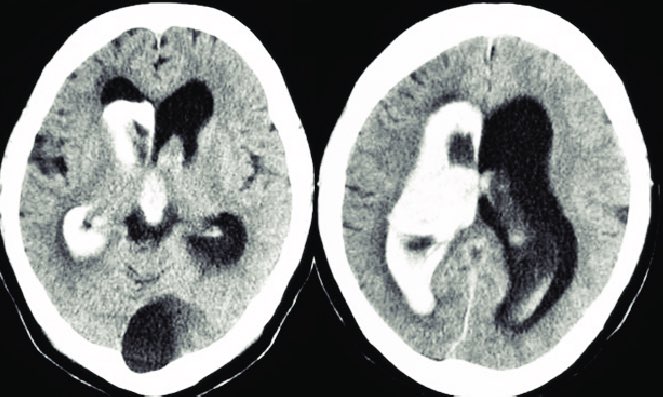

أنواع hematomas والأشعة لكل نوع

الحرف الرابع "V”

ويقصد فيه ال Ventricle

لازم نستبعد ان مافي دم في الحجرات زي اللي يصير في حالات

Interventricular hemorrhage

ولازم نركز على حجم حجرات الدماغ ونتأكد أنها متساوية

ومافي hydrocephalus